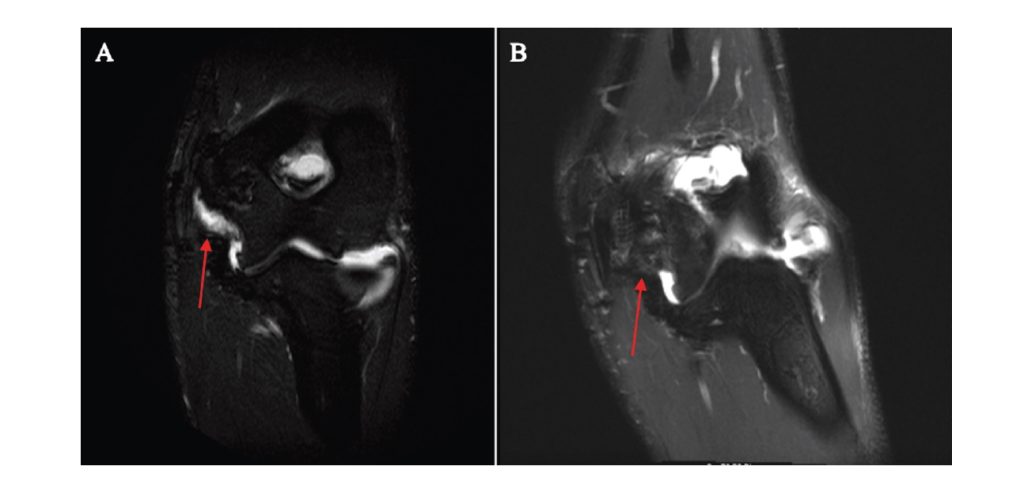

A Novel Ultrasound Assessment Technique of the Ulnar Collateral Ligament to Account for the Valgus Stress Effect of Gravity on the Medial Elbow

Background: The ulnar collateral ligament (UCL) of the elbow is commonly injured in baseball athletes. When assessed in the supine abducted and externally rotated (ABER) position using stress ultrasonography (sUS), even before applying a valgus load, gravity pulls on the forearm, creating an initial valgus load that may distort the resting joint space measurement. Purpose/Hypothesis: The purpose of this study was to measure the valgus stress effect of gravity on the resting joint space and determine if a varus-stressed joint space provides a better baseline measurement. It was hypothesized that there would be a greater resting joint space in the throwing arm in the ABER position as a result of UCL laxity but no difference in joint space under varus stress compared to the nonthrowing arm.